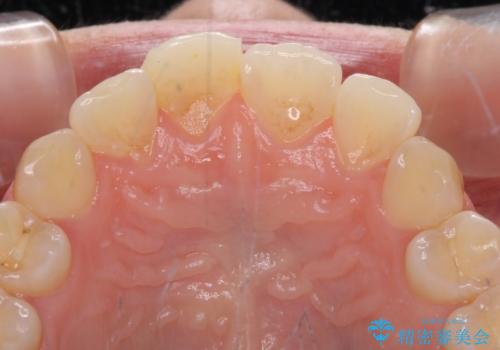

転んで前歯の先端1/3ほどが欠けており、近医にて応急処置としてコンポジットレジン修復がされていました。

審美性や舌触り、今後の歯への負担などを考え、オールセラミッククラウンにて補綴治療を行うこととしました。